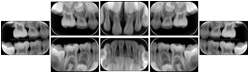

Intra-oral radiography typically involves acquisition of multiple images of various parts of the dentition. Many digital radiographic systems offer customized templates that are used for displaying the images in a study on the screen. These templates may also be referred to as mounts or view sets. The Structured Display Object represents a standard method of encoding and exchanging the layout and intended display of Structured Displays. A structured display object created in this manner could be stored with a study and exchanged with images to allow for complete reproduction of the original exam.

1. A patient visits a General Dentist where a Full Mouth Series Exam with 18 images is acquired. The dentist observes severe bone loss and refers the patient to a Periodontist. The 18 images from the Full Mouth Series along with a Structured Display are copied to a DICOM Interchange CD and sent with the patient to see the specialist. The Periodontist uses the CD to open the exam in his Dental Radiographic Software and consults via phone with the General Dentist. Both are able to observe the same exam showing the images on each user's display using the exact same layout.

Intra-oral Full Mouth Series Structured Display

Figure OO-1. Intra-oral Full Mouth Series Structured Display